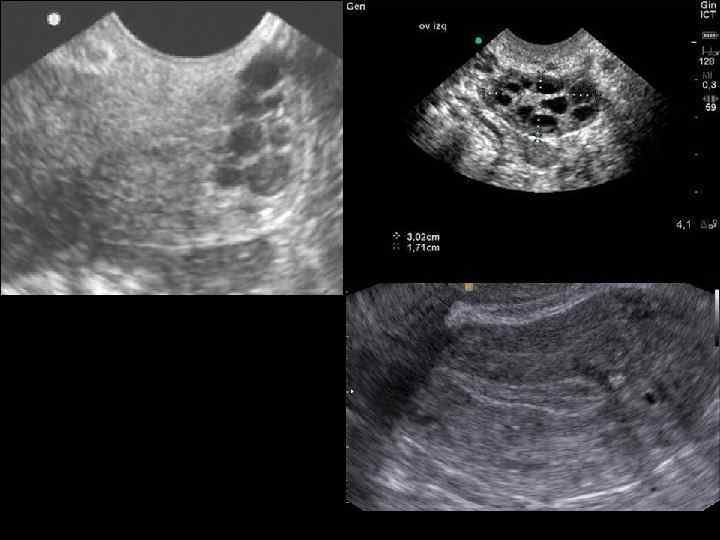

- МРТ при эндометриозе может оказать большую помощь в диагностике. - УЗИ. Для эндометриальных кист яичников характерна плотная капсула, размеры до 10– 12 см, гиперэхогенное содержимое в виде мелкодисперсной взвеси. При эндометриозе матки выявляют участки повышенной эхогенности в миометрии, неравномерность и зазубренность границ мио и эндометрия, округлые анэхогенные включения до 5 мм в диаметре, при узловых формах ― жидкостные полости до 30 мм в диаметре.